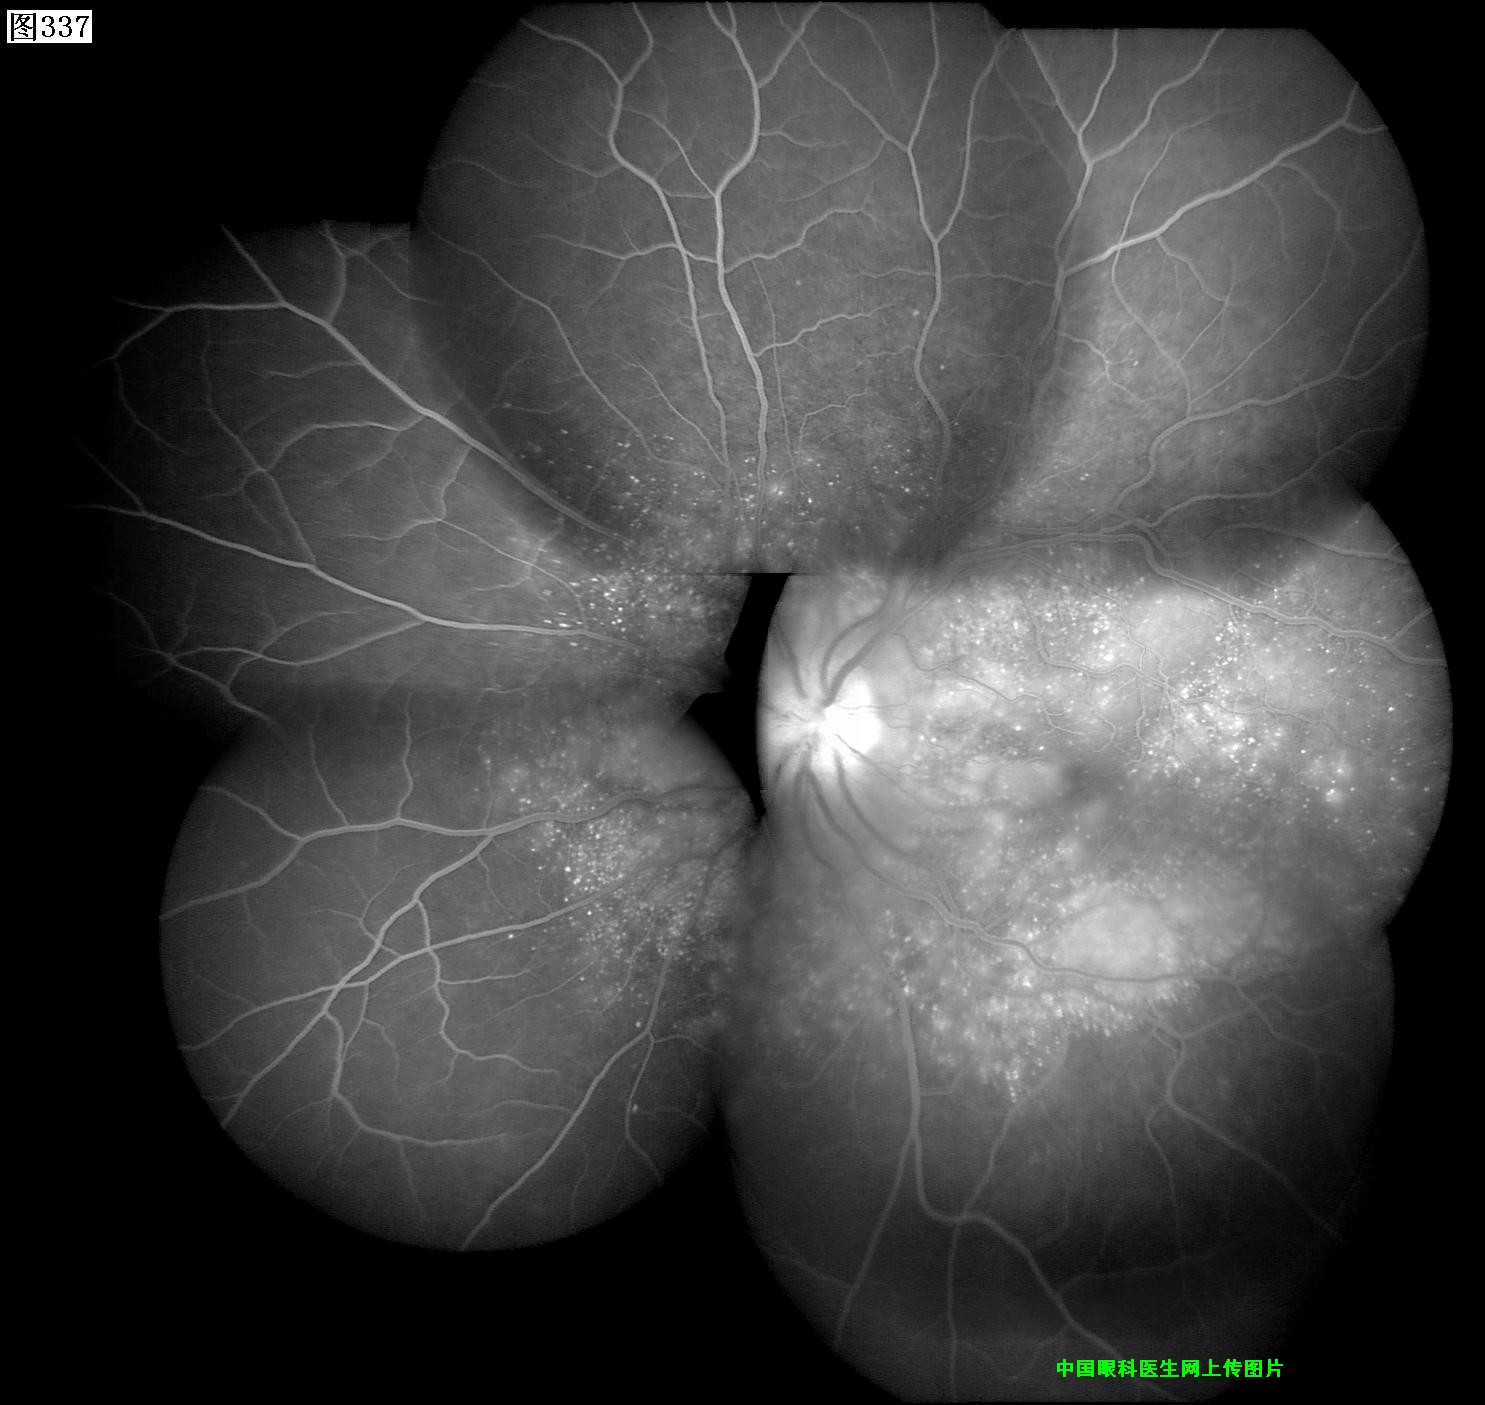

337 338 339 340